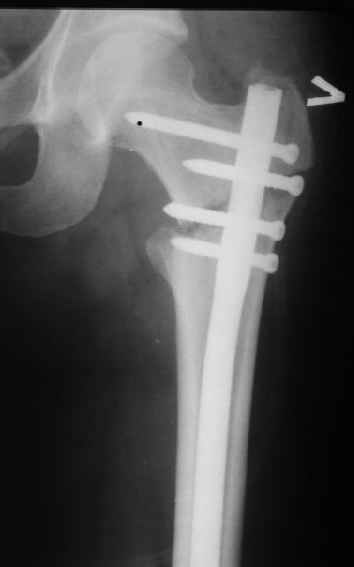

Могу скромно напомнить о существовании стержня нашей модификации.

В частности, на проксимальном конце сделано еще одно дополнительное статическое отверстие. Можно ввести в проксимальном отделе 4 винта, из них 3 статические (2 в круглые отверстия и 1 по нижнему краю овального). Картинки в приложении. На дистальном конце стержня тоже кое-что улучшено. Спрашивайте в аптеках, как говорится. Выпускается предприятием "ЦИТО" (Москва), то есть это малобюджетное решение.

Конечно, мы не синтезируем остеопорозые вертельные переломы согласно прилагаемому примеру, винты 6 мм вырежутся. Но у более молодых при хорошем качестве кости такие или подобные гвозди с поперечным расположением винтов вполне применимы для меж- и подвертельных переломов.